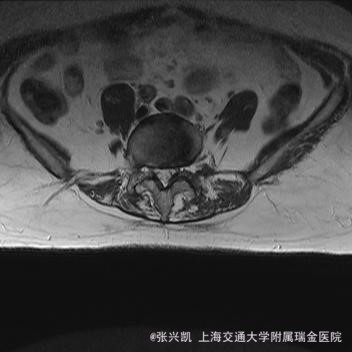

主诉:双下肢麻木7年,腰部酸痛无力 现病史:女性患者,70岁,患者诉腰背无力十几年,约于7年前无明显诱因下出现下肢麻木,站立位加重。后出现腰臀部僵硬,弓背加重,行走距离较短, 不足百米,几年前外院检查诊断为腰椎管狭窄,具体不详。

查体:侧弯畸形,右臀部及右下肢麻木疼痛,腰部活动受限,难以站立。右侧支腿抬高试验50°。双下肢肌力肌张力可。 辅助检查: 磁共振:L1-5,L5-S1腰椎椎间盘突出,腰椎退变,腰椎侧弯

诊断: 腰椎侧弯,腰椎间盘突出 治疗:1期微创侧路椎体融合术+2期 微创后路经皮内固定术